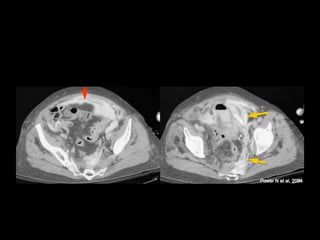

TRAUMA VESICAL

• 22% Trauma urologico

• Traumatismos cerrados representan 67% y el

86%

• 70-90% asociacion con fractura pelvica

• Trauma penetrante 14-33%

• Iatrogenos 3-4%

• H-M 3:1

• Niños aumenta frecuencia

Extraperitoneal

Intraperitoneal

Diagnostico

• Signos y síntomas

Incapacidad para orinar

Hematuria macroscópica

Dolor abdominal

Dolor pélvico

Abdómen agudo